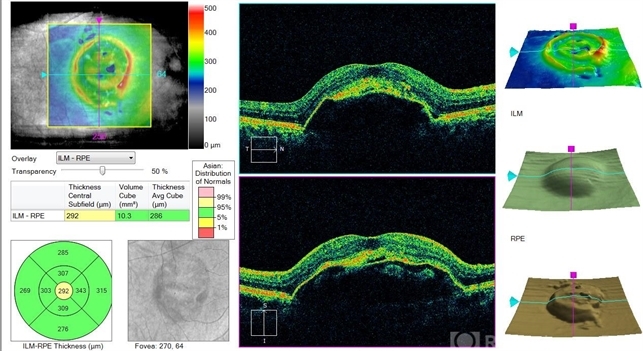

- optical coherence tomography (OCT)

- Eitae Kim, BOIM retinal center, Pureun eye hospital

Optical coherence tomography system

Cirrus, Zeiss - Description

- Initial OCT of 78-year-old male with advanced AMD.